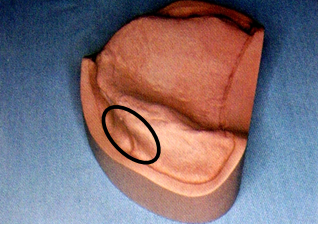

6.磨牙后垫(retromolar pad)

位于下颌最后磨牙牙槽嵴远端的粘膜软垫,覆盖在磨牙后三角上,由疏松的结缔组织构成,含黏液腺。

磨牙后垫的形态和位置比较稳定,作为排人工牙时的解剖标志;垂直向:下颌第一磨牙的颌平面与磨牙后垫的1/2处等高;

前后向:下颌第二磨牙应位于磨牙后垫前缘;

颊舌向:磨牙后垫颊面、舌面向前与下颌尖牙的近中面形成一个三角形。